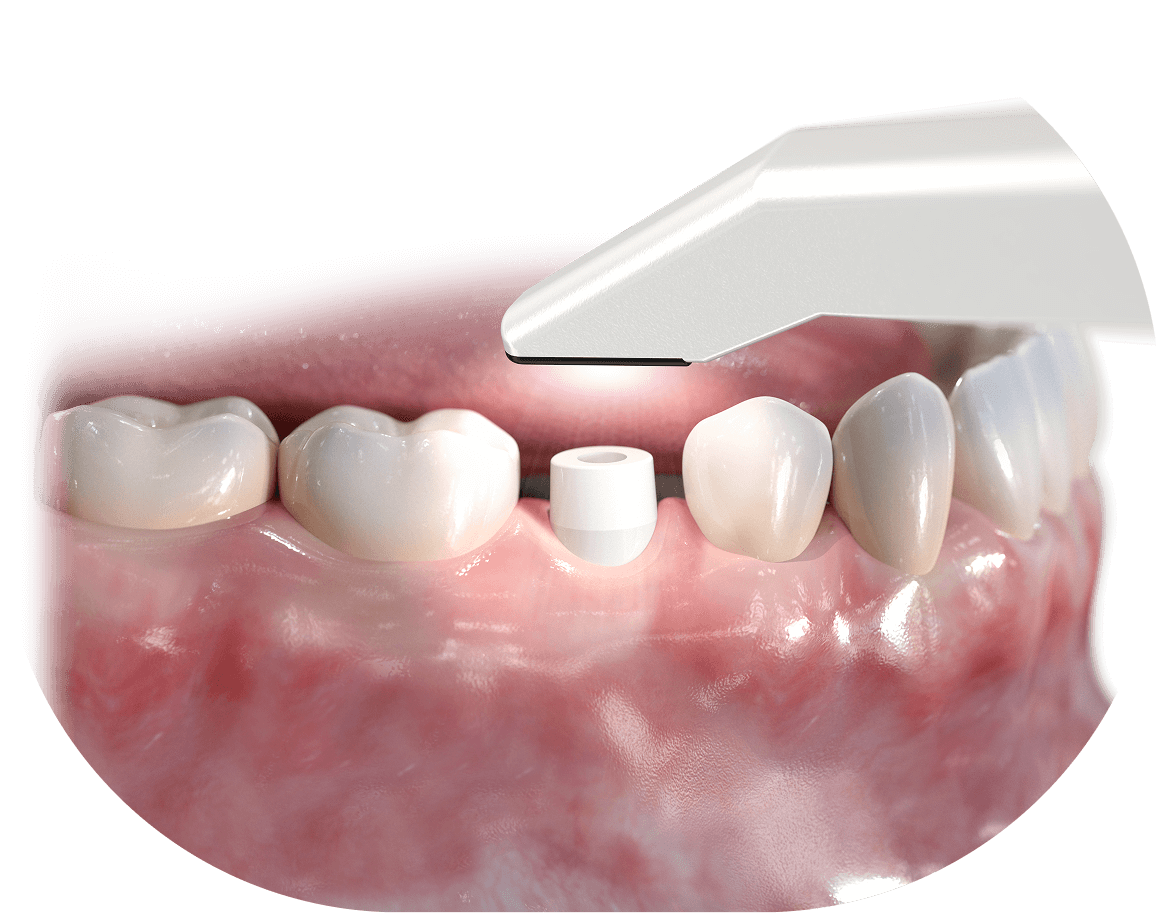

Implant to niewielkich rozmiarów śrubka, która wszczepiona w kość szczęki lub żuchwy zastępuje funkcję utraconego korzenia zęba. Implanty zębów produkowane są najczęściej z tytanu. To bezpieczny i biozgodny dla naszego organizmu materiał, który cechuje dodatkowo duża wytrzymałość mechaniczna. Pozwala to na prawidłowe zrośniecie się implantu z kością, a po wgojeniu – na trwałe umocowanie rekonstrukcji korony brakującego zęba.

Implanty zębów to najczęściej niewielkich rozmiarów śrubki, które wszczepione w kość szczęki lub żuchwy zastępują utracony korzeń zęba. Współczesne implanty zębowe produkowane są głównie z tytanu. To bezpieczny i biozgodny dla naszego organizmu materiał, który cechuje dodatkowo duża wytrzymałość mechaniczna. Pozwala on na prawidłowe zrośnięcie się każdego implantu z kością, a po wgojeniu – na stałe umocowanie rekonstrukcji koron brakujących zębów. Bezpieczeństwo ich użytkowania mierzone jest odsetkiem prawidłowo wgojonych implantów, który szacowany jest obecnie na 95–99%, co sprawia, że leczenie implantologiczne jest bardzo przewidywalne.